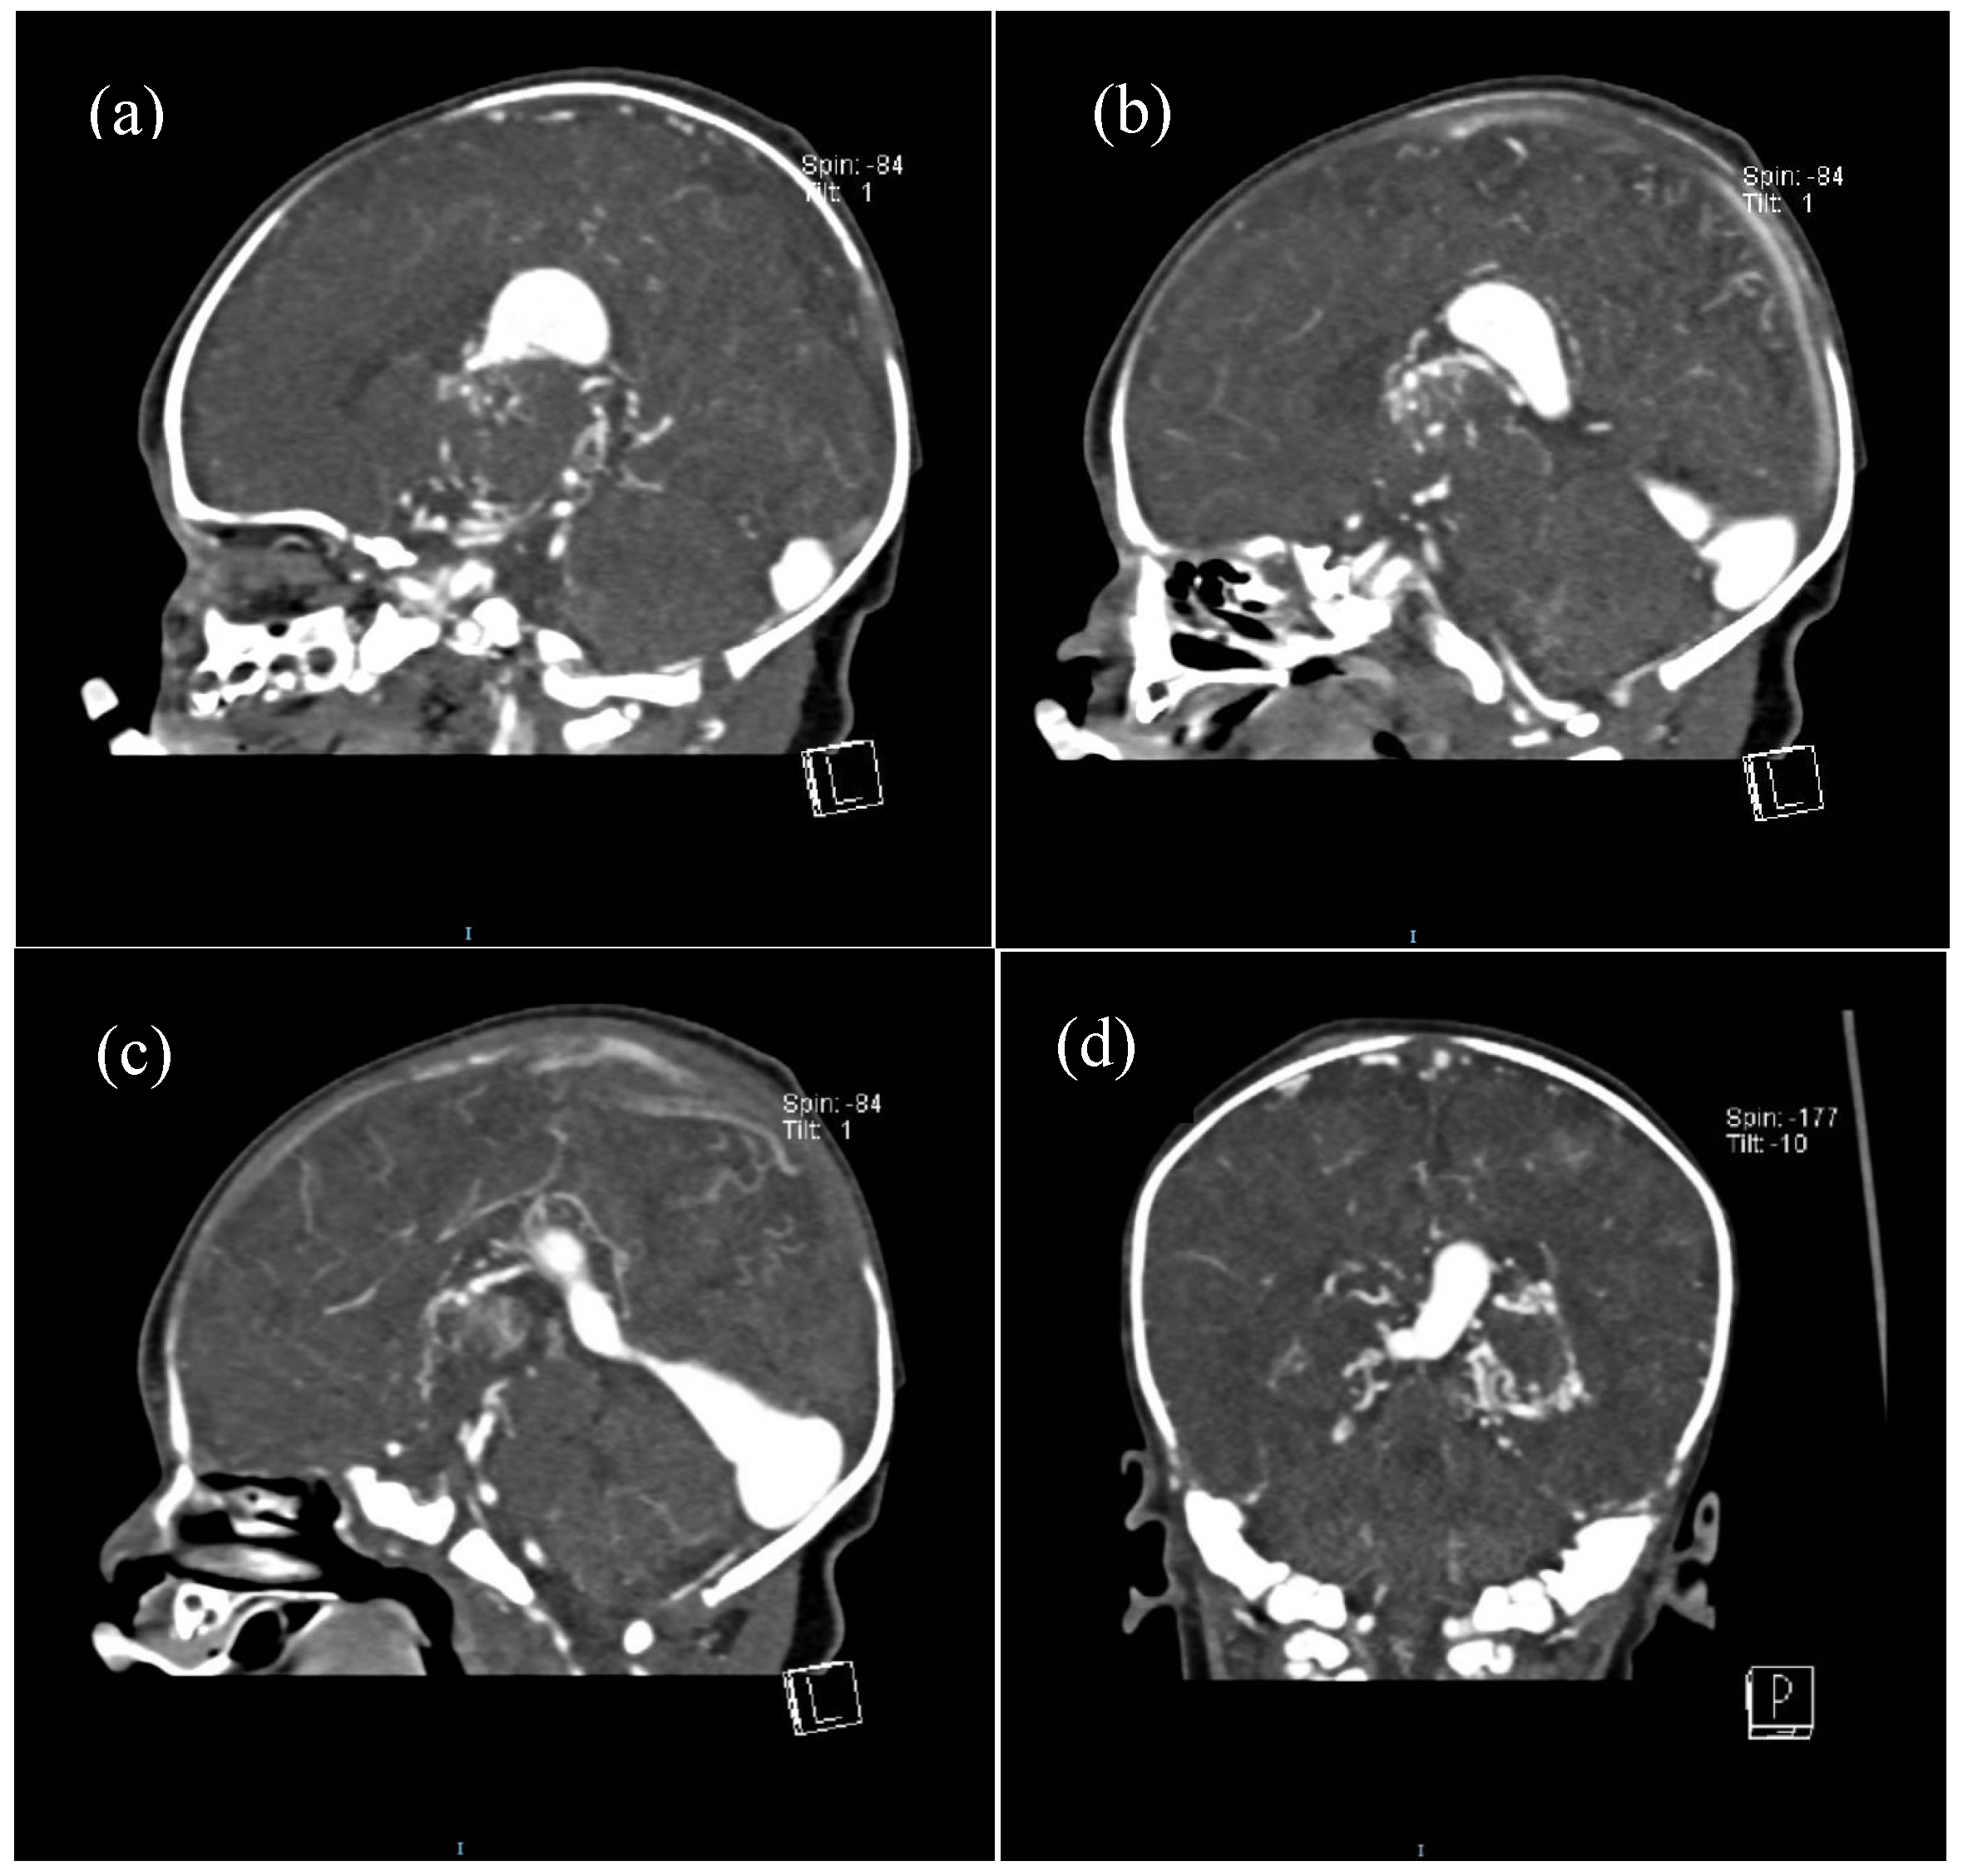

Half of the patients were diagnosed antenatally (by ultrasound or fetal MRI) and half of them postnatally, most frequently by cerebral ultrasound or after auscultation of a cardiac murmur followed by heart ultrasound displaying diastolic steal from the thoracic or descending aorta into the carotid territory towards cerebral circulation. The general aspect described was that of a saccular structure located at the level of the quadrigeminal tank with both arterial and venous Doppler signals, communicating with the large cerebral sinuses and having numerous arterial and venous collaterals (see Figure 1 and Figure 2).

For some patients, the diagnosis was completed by brain MRI cerebral angio-CT (with iodinated radiocontrast agent at a concentration of 300 mg I/mL) methods for a better understanding of the Galen vein aneurysm morphology and its anatomical relations (see Figure 3, Figure 4, Figure 5 and Figure 6). Three of five patients who performed superior imaging techniques had large varieties of the Galen vein malformation, with variable degrees of compressive effect and secondary changes in the appearance of the midline and ventricular symmetry. Three patients presented with corpus callosum dysgenesis and three others with engorged arteries of the Willis polygon and enlarged pericerebral venous sinuses. None of the patients underwent an angiographic study of the arteriovenous malformation they had been diagnosed with in order to conceivably facilitate the perspectives of endovascular embolization in a center with expertise.

Figure 6. Contrast cerebral CT scan: (ac). Progression of filling with contrast substance of the VoGM (sagittal view), (d). VoGM filled with contrast in coronal plane (posteroanterior view).